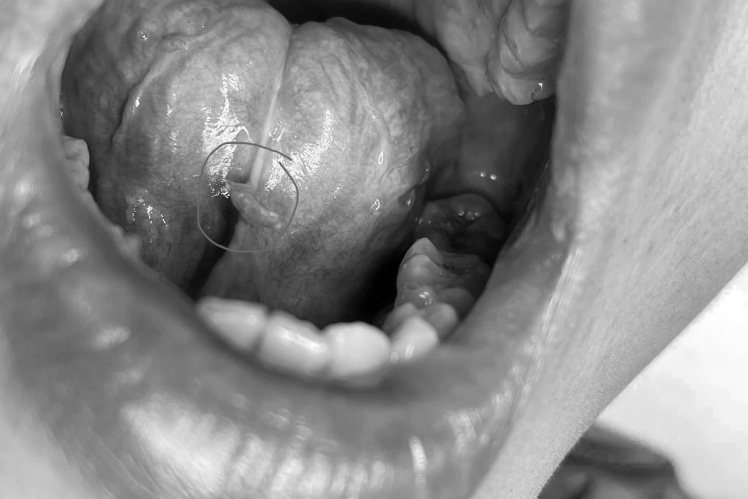

Anh L.V.K (30 tuổi, trú tại Hà Đông, Hà Nội) đến khám bệnh với triệu chứng ngứa họng, cảm giác có vật gì rất vướng mỗi khi nhai nuốt thức ăn, vị trí kẽ chân răng, dây hãm lưỡi mọc u nhú, ngày càng to, dễ chảy máu. Từ ngày xuất hiện u nhú ở miệng, anh có cảm giác hôi miệng, ăn uống sinh hoạt khó khăn và rất lo lắng. Đến khám tại Bệnh viện Răng Hàm Mặt, anh được bác sĩ giới thiệu sang điều trị chuyên khoa da liễu.

Theo thạc sĩ, bác sĩ Nguyễn Tiến Thành, Thành viên Hội da liễu Việt Nam, khi quan sát tổn thương của bệnh nhân bác sĩ nghi ngờ u nhú, lây nhiễm qua đường tình dục. Kết quả xét nghiệm bệnh nhân mắc sùi mào gà. Khi nghe bác sĩ tư vấn bệnh, anh K. vô cùng bất ngờ.

Sùi mào gà bắt đầu bởi biểu hiện tổn thương sẩn mềm màu da, hồng hoặc màu nâu, đường kính khoảng một vài mm. Sau vài tuần đến vài tháng, các tổn thương có thể hợp lại thành mảng lớn hơn hay còn được gọi tổn thương dạng súp lơ - mào gà.

Ngoài ra, sùi mào gà có thể xuất hiện ở vị trí niêm mạc, bán niêm mạc khác: mắt, miệng ( lưỡi, kẽ chân răng, niêm mạc má),